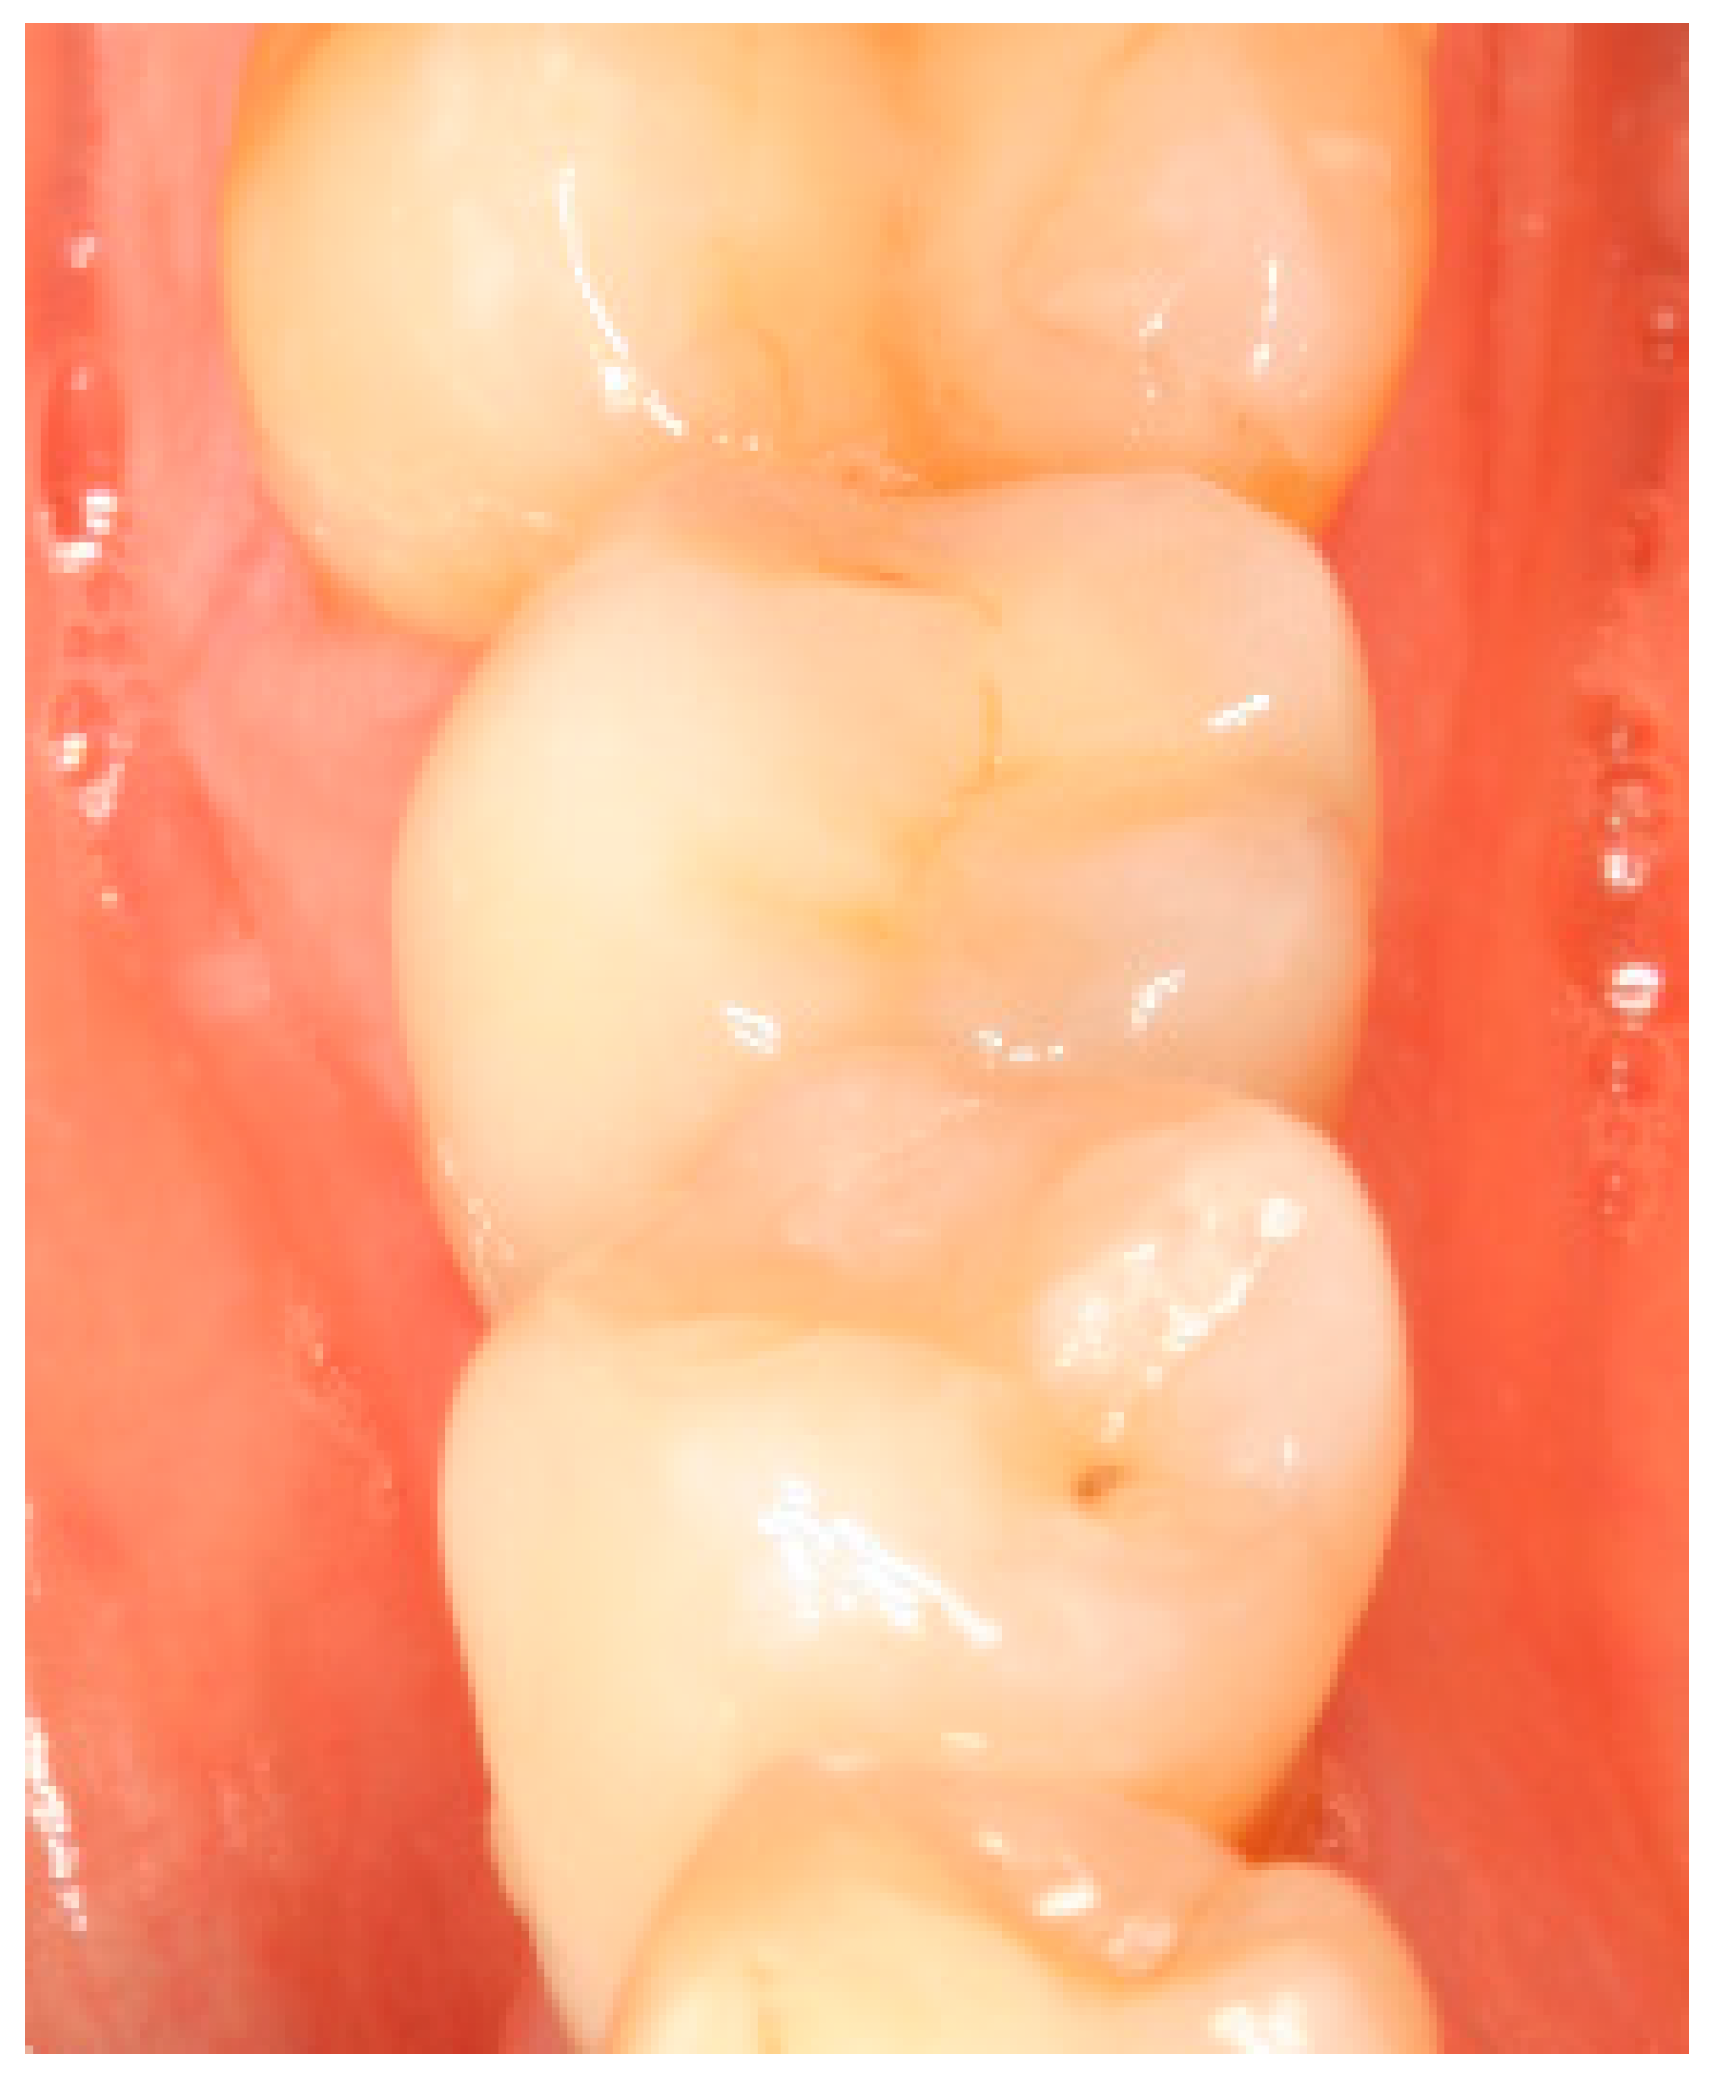

Figure A13.

Figure A16.

Figure A19.

Figure A22.